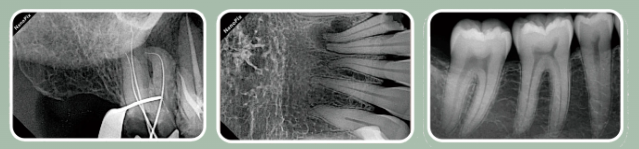

Клинические изображения

Чёткое изображение с высоким разрешением и фокальным пятном 0.4 мм